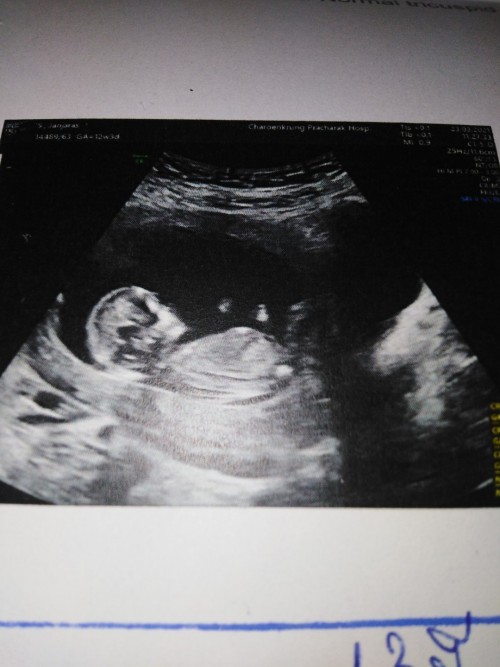

12วีค